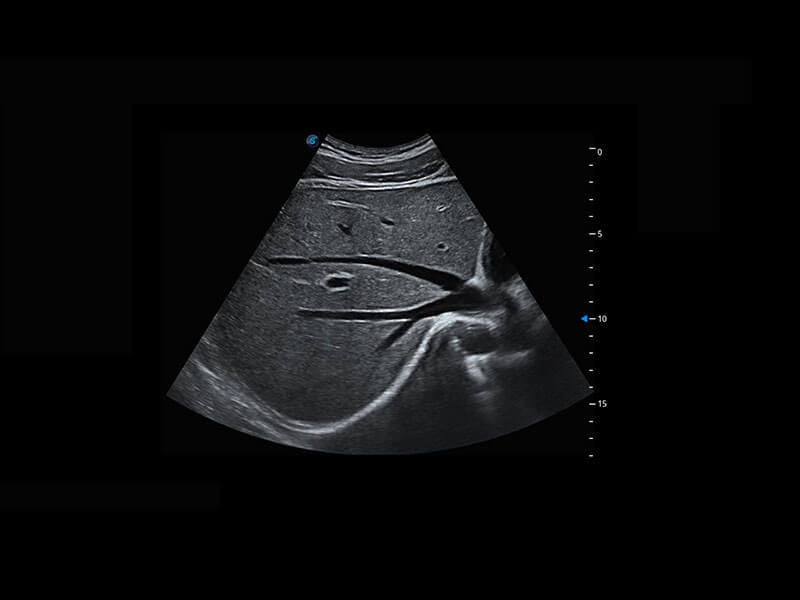

P60优异的图像质量搭载专科探头,在妇科基础疾病的诊断、卵泡生长的监测、输卵管通畅情况的判别等方面为您提供生殖应用方案。

腔内妇科-卵巢